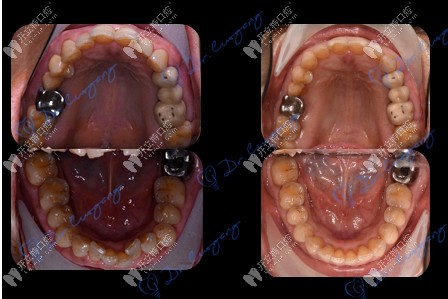

牙齒矯正前后對(duì)比

經(jīng)過(guò)檢查,王阿姨非常符合牙齒矯正所需的口腔條件。這得益于她幾十年來(lái),堅(jiān)持在飯后使用牙線、沖牙器來(lái)清理食物殘?jiān)?!---->腔衛(wèi)生,因此牙齒沒(méi)有出現(xiàn)松動(dòng)脫落的現(xiàn)象,牙槽骨情況也十分健康。

歷經(jīng)一年半的佩戴,如今,王阿姨已經(jīng)順利地摘下牙套,牙齒恢復(fù)了整齊,并保持著健康的口腔狀態(tài)。她還經(jīng)常向身邊家人朋友們科普牙齒保健知識(shí),帶動(dòng)他們關(guān)注口腔健康。